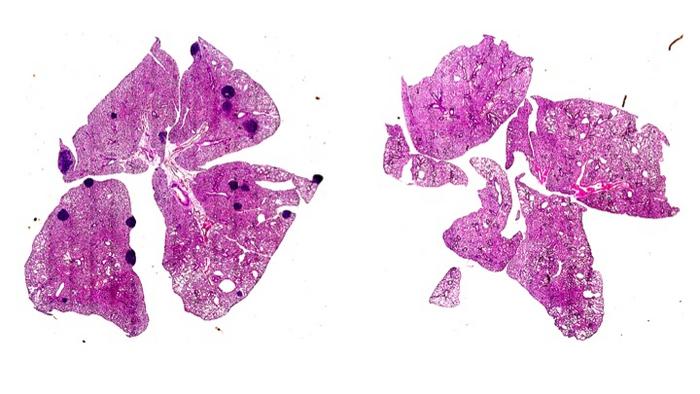

Mice with breast tumours developed metastatic cancer in their lungs (visible as dark deposits), whereas this was prevented in mice lacking ARHGEF1 - a key protein involved in suppression of T cell immunity by the clotting factor Thromboxane A2.

The researchers previously screened 810 genes in mice and found 15 that had an effect on cancer metastasis. In particular, they found that mice lacking a gene which produces a protein called ARHGEF1 had less metastasis of various primary cancers to the lungs and liver.

This new research found that aspirin prevents cancers from spreading by decreasing TXA2 and releasing T cells from suppression. They used a mouse model of melanoma to show that in mice given aspirin, the frequency of metastases was reduced compared to control mice, and this was dependent on releasing T cells from suppression by TXA2.